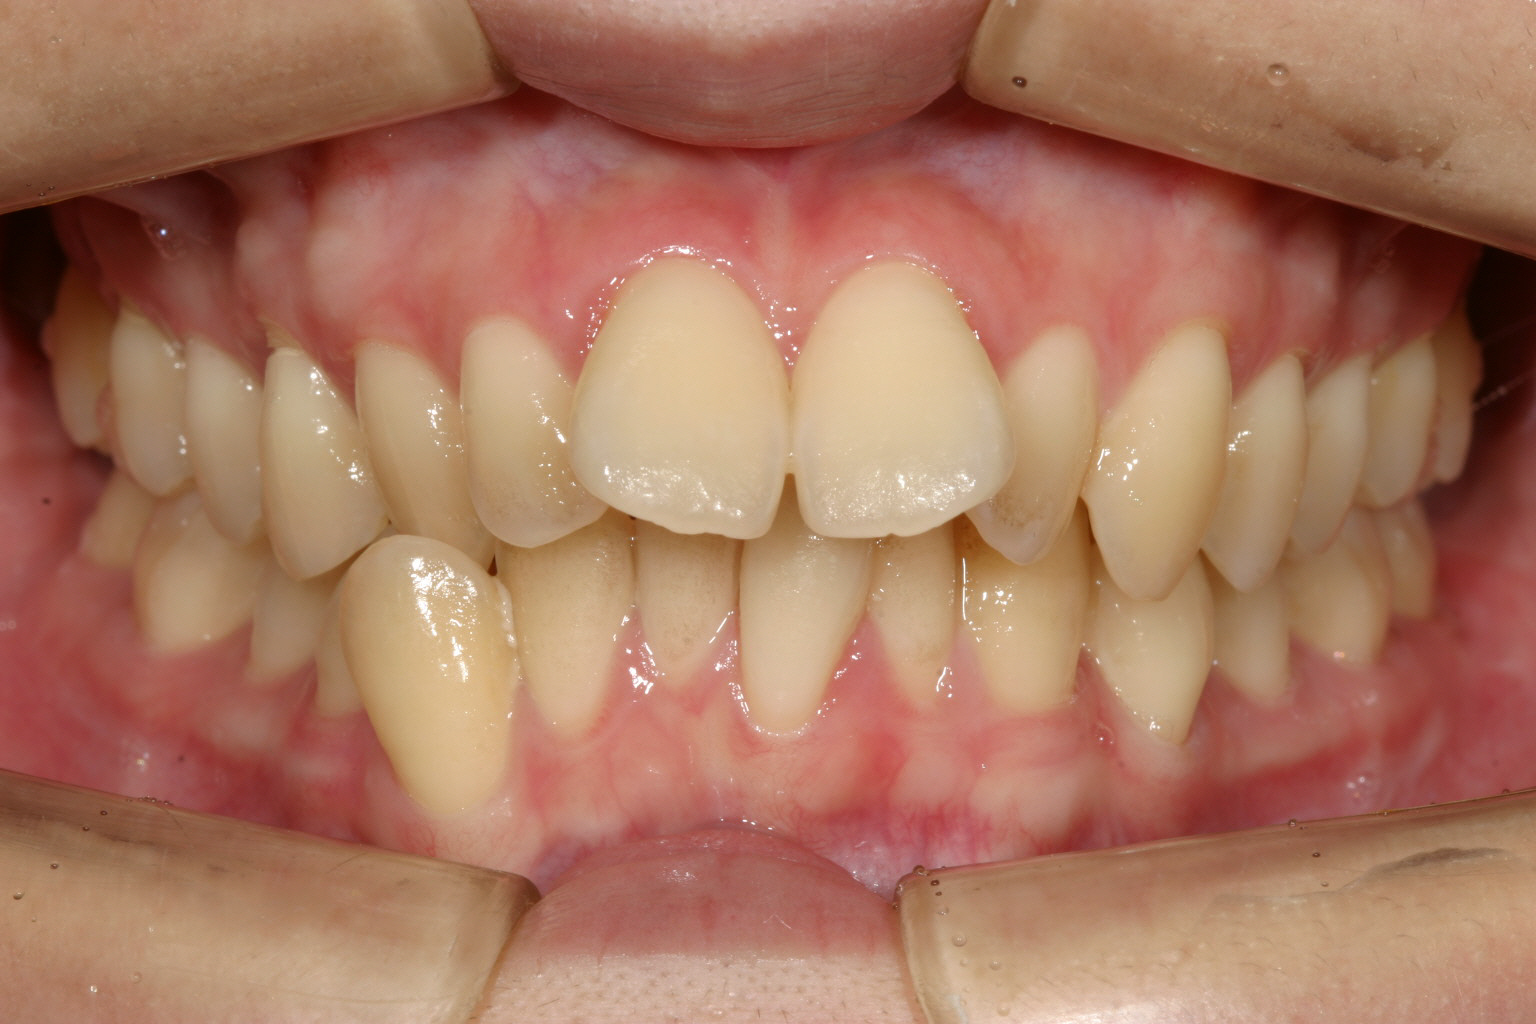

かなりヘビーな翼状捻転です。

下顎前歯の叢生もかなりのもんです。 と言う事でワイヤー矯正を選択しました。

出っ歯観が患者様が一番気になるところです。